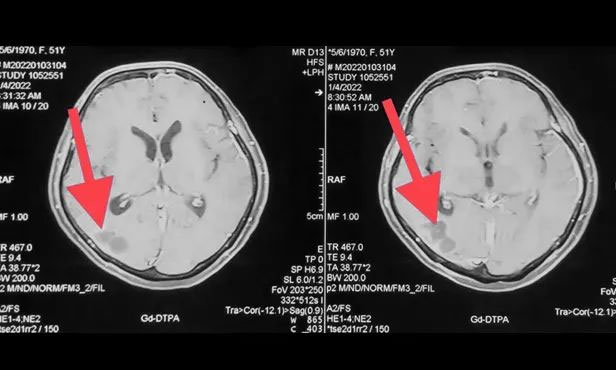

▲ 刚入院时病灶影像

▲ 完成穿刺,黑色囊液被顺利引流

▲ 经复查,病灶较前明显缩小

按照肿瘤复查的标准,复查影像显示王女士颅内病灶相较于来院时明显缩小。家属为此特意向陈琦主任致谢,并对医院的治疗和服务表达了充分肯定。